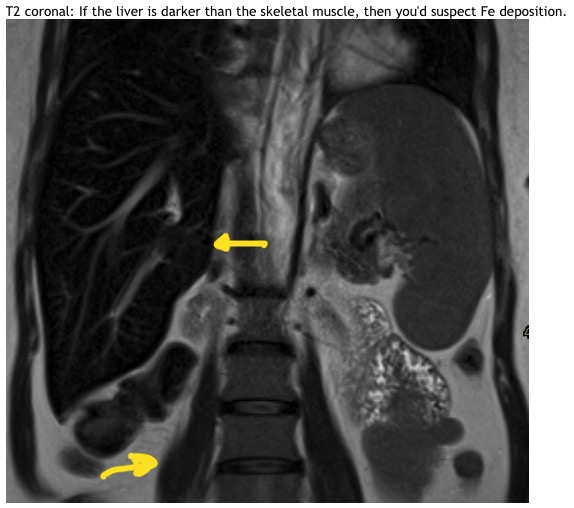

T2 coronal: If the liver is darker than the skeletal muscle, then you'd suspect Fe deposition.